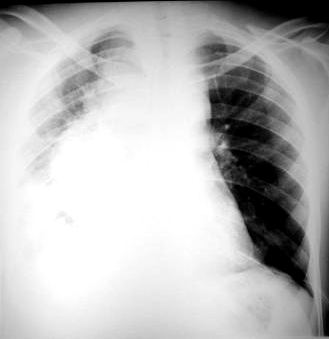

Rx torax PA:

• Observamos radiopacidad homogénea en hemitorax izquierdo, el cual se aprecia de mayor volumen que el hemitórax derecho,  que produce desviación contralateral de las estructuras mediastinales.

• En el lado derecho se aprecia la compresion del pulmon por el derrame contralateral y observamos una lesion de aspecto redondeada, mediastinal, heterogénea, no se aprecia derrame pleural derecho

Rx torax: tumor del pulmon